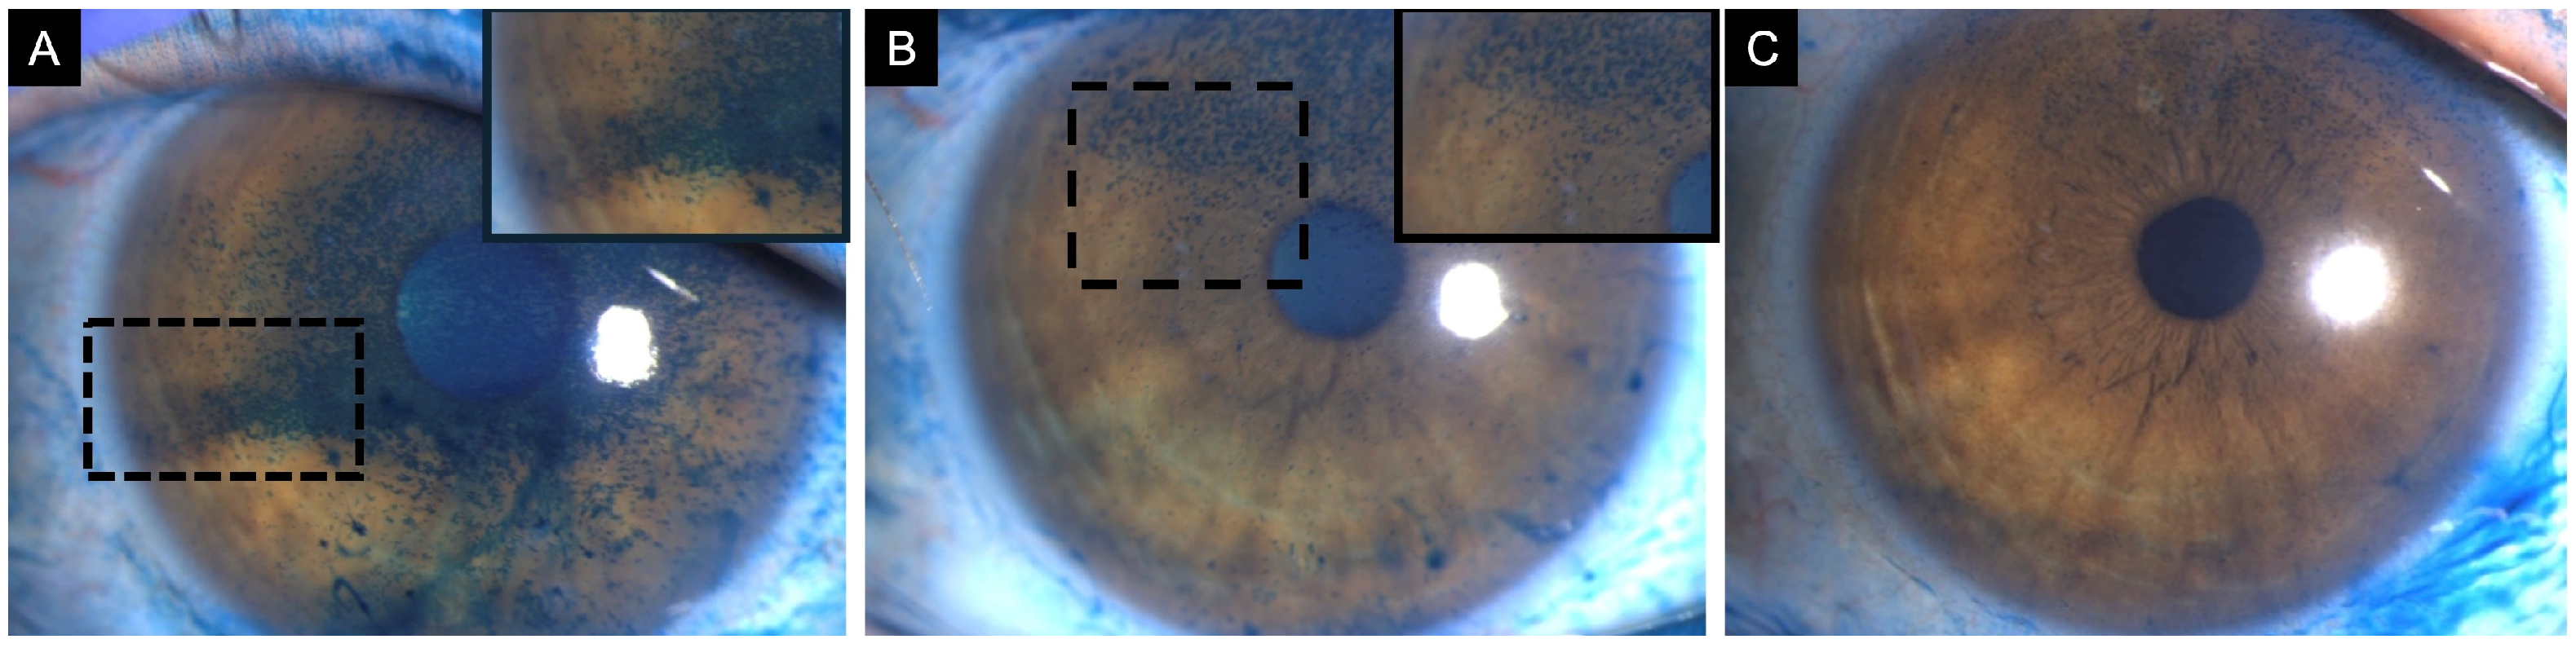

Figure 1.

Clinical images of an 82-year-old female with neurotrophic keratitis (Cochet–Bonnet corneal sensitivity: 20 mm). (A) Corneal fluorescein staining demonstrates superficial punctate keratitis inferiorly (3 points), temporally (1 point), nasally (1 point), and centrally (1 point), for a total National Eye Institute (NEI) grading score of 6. (B) Corneal epithelial optical coherence tomography (OCT) map shows diffuse epithelial thinning, as represented by the extensive blue zone. Cool-toned colors (i.e., dark blue) repesent thinner areas with warm colors (i.e., red and orange) representing thicker areas of epithelium. (C) In vivo confocal microscopy (IVCM) at the level of the sub-basal nerve plexus reveals markedly reduced corneal nerves.